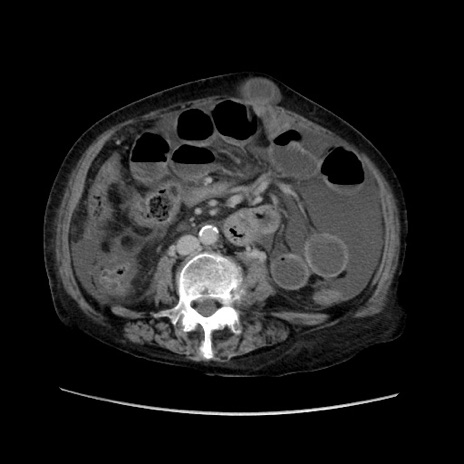

冠状断像

【症例】80歳代 女性

【主訴】腹部膨満感

【現病歴】他院にて肝硬変にてフォロー中。1週間前から便秘、腹部膨満感、臍部腫瘤あり受診となる。

【既往歴】肝硬変

【身体所見】腹部膨隆あり、皮膚変化なし、疼痛なし。

【データ】WBC 4600、CRP 0.25